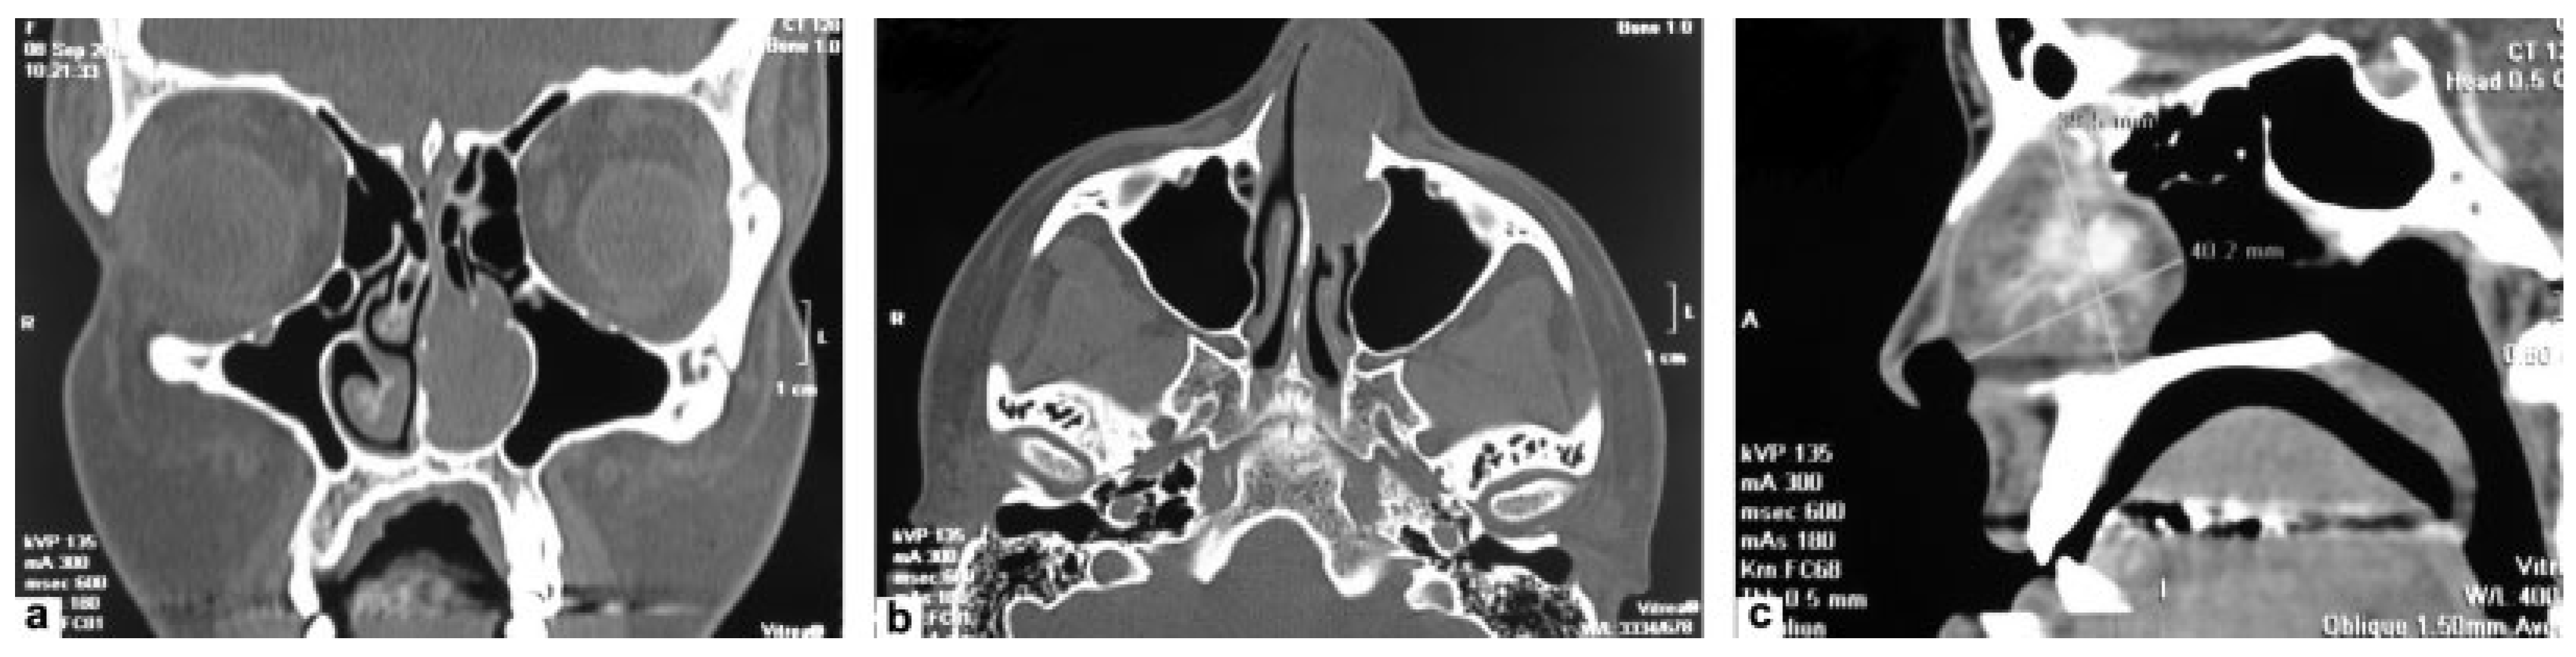

Extranasopharyngeal Angiofibroma Arising from the Anterior Nasal Septum in a 35-Year-Old Woman

Case Report